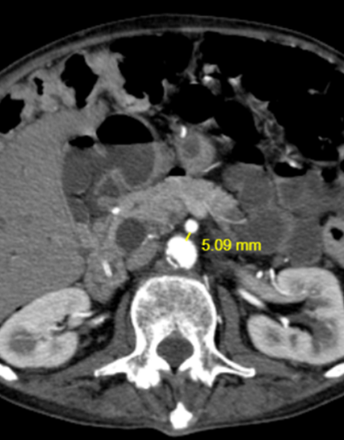

Wilkie’s syndrome, changing perspectives in image visualization

The superior mesenteric artery syndrome is an uncommon entity included in the spectrum of vascular syndromes. The low presentation, variety of unspecific symptoms, and shortage of bibliography presents a challenging diagnosis for both clinicians and radiologists. Our aim is to present a 63 years-old male patient with pancreatitis history and repeated symptoms.